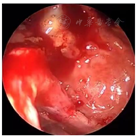

口腔检查:口腔颌面部左右不对称,左侧鼻旁区明显隆起,按压乒乓球样感,双侧颞下颌关节无弹响,无压痛。口内见12-23前庭沟处膨隆,大小约4.2 cm×2.0 cm,边界清,质软,有轻微压痛,22-24腭侧球形膨隆,大小约1.5 cm×1.5 cm,边界清,质软,可触及波动感,无压痛。22唇侧有一瘘管,挤压有脓液溢出。鼻内镜检查:鼻腔黏膜略充血,左侧鼻底及下鼻道见明显隆起(图4),将左侧下鼻甲推向外上方,鼻中隔向右侧偏曲,左侧鼻道较宽敞,中鼻道略隆起,未见分泌物。CBCT示:12-24根尖区可见3.7 cm×1.6 cm大小的低密度影像,边界清楚,密度均匀,内见不完全的骨间隔影,肿物累及左侧鼻底及鼻腔外侧壁,左侧上颌窦内见液平面。

入院后完善术前常规检查,于次日在局麻下行切开引流术,阿替卡因肾上腺素行21-22前庭沟黏膜下局部浸润麻醉,麻醉显效后,自21-22前庭沟处切开黏膜及黏膜下层至囊腔约3 mm水平切口,见大量黄色分泌物溢出,取部分脓液做细菌培养,大量生理盐水冲洗至冲洗,留置橡皮引流条,术后常规予以抗生素控制感染。4 d后检查前庭沟切口处已愈合。经耳鼻咽喉科与口腔颌面外科会诊,决定行鼻内镜下左侧鼻底、下鼻道共同开窗肿物切除术。术中先用彭氏电刀电凝左侧鼻底及下鼻道隆起处黏膜(图5),剥离子自隆起处外侧刺破黏膜进入囊腔,见大量囊液流出,囊液呈浅褐色,略浑浊,吸净囊液后,向后扩大开窗口,保留后部黏膜瓣。剥离部分囊壁送病理检查,清除病变组织后,发现位于囊腔前下壁的不完全的骨间隔隆起(图6)。剥离子在囊肿的左侧上部探查见上颌窦内下骨质缺损,由此刺破软组织进入上颌窦,见有黏液涕流出,扩大上颌窦开窗口,动力系统清除病变组织,使囊肿腔与上颌窦形成一个腔(图7),修剪后部蒂瓣,使之正好贴敷于囊腔后壁(图8),反复生理盐水冲洗术腔,检查无残留,膨胀海绵填塞。手术过程见视频。手术顺利,术后继续行抗生素控制感染,48 h抽出鼻腔膨胀海绵,检查见鼻底及上颌窦开窗口开放良好,腔内有少许血性分泌物,黏膜略水肿。术后病理镜下见被覆鳞状上皮,间质内见急慢性细胞浸润(图9)。术后4 d患者康复出院。